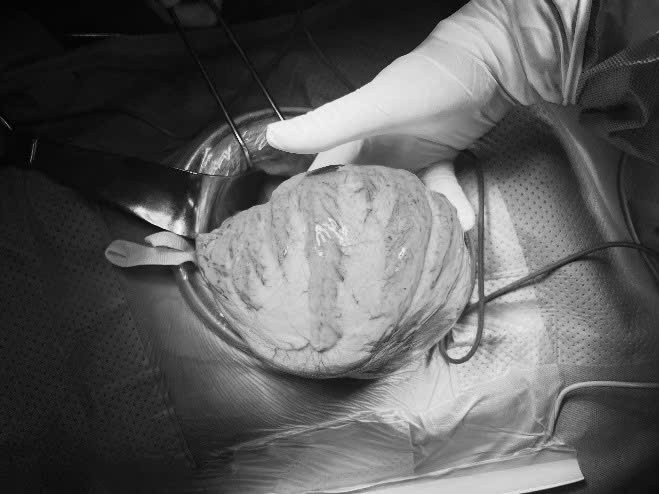

| Khối phân gây giãn toàn đại tràng. (Ảnh BV 108) |

Qua thăm khám tình trạng bụng phát hiện khối bất thường kích thước 20x 30cm, mật độ chắc. Trên hình ảnh cắt lớp vi tính bụng, khối bất thường là khối phân tích tụ lâu ngày tại đại tràng sigma gây giãn toàn bộ khung đại tràng. Đường kính quai đại tràng giãn lớn nhất là 12cm. Chẩn đoán: Tắc ruột thấp do khối phân lớn vùng tiểu khung/ Bệnh lý megacolon.

Bệnh nhân đã được bù dịch điện giải, nuôi dưỡng tĩnh mạch trước mổ. Trong mổ thấy toàn bộ khung đại tràng giãn lớn đường kính >10 cm; thành dày; trương lực có giảm. Khối phân kích thước khoảng 20 x 30 cm ở đại tràng sigma. Bệnh nhân được tiến hành sinh thiết tức thì xác định vị trí tổn thương. Cắt đại tràng sigma cùng khối phân. Sau mổ bệnh nhân ổn định và đã ra viện.